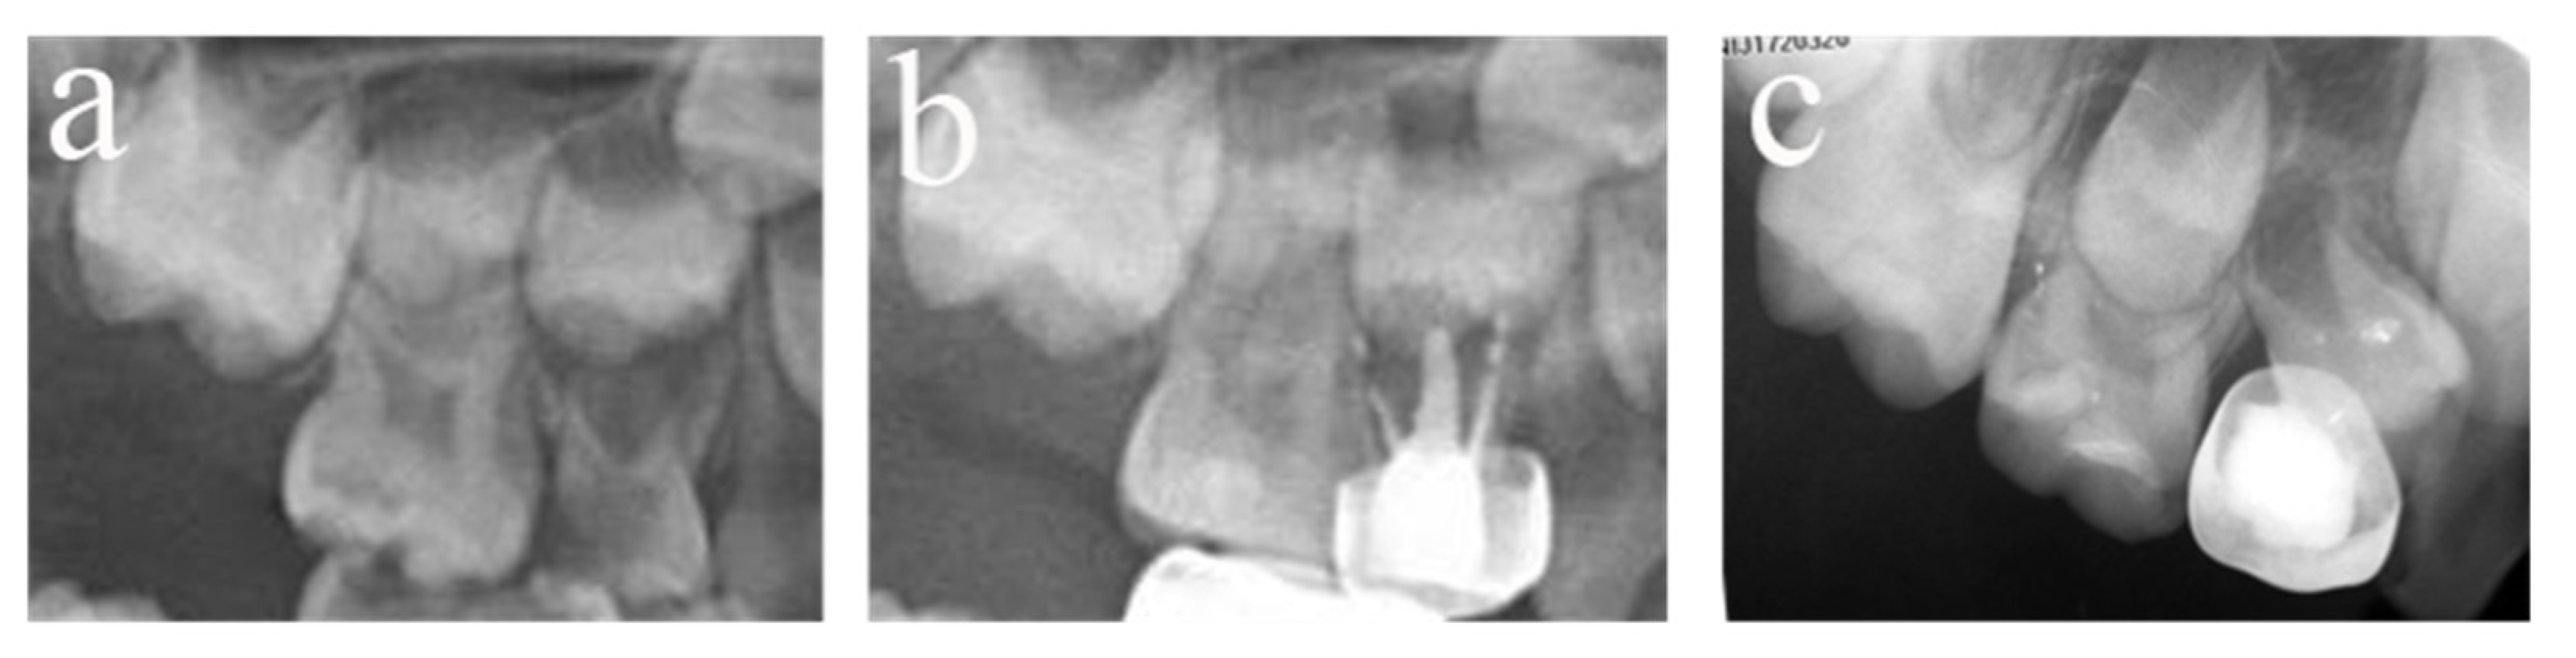

Figure 4.

#51, #61, and #62 received pulpectomies under DGA with a 12-month follow-up period (57-month-old female child). (a) Preoperative radiograph and #61 revealed periapical radiolucency. (b) Two weeks later, the postoperative radiograph showed underfilling in #61 and optimal filling in #51 and #62. (c) Radiograph taken 12 months postoperatively showing nothing abnormal about #62 and a periapical radiolucency surrounding the root apical of #51. Moreover, a radicular cyst occurred surrounding the apical root of #61, and the eruption direction of #21 was altered. Pulpectomies in #62 succeeded but failed in #51 and #61.